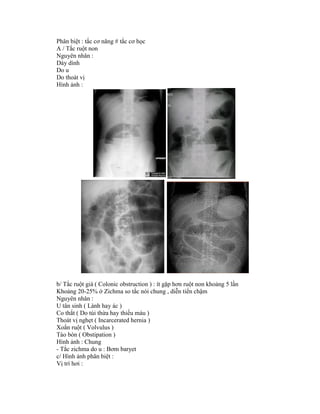

A / Tắc ruột non

Nguyên nhân :

Dày dính

Do u

Do thoát vị

Hình ảnh :

b/ Tắc ruột già ( Colonic obstruction ) : ít gặp hơn ruột non khoảng 5 lần

Khoảng 20-25% ở Zichma so tắc nói chung , diễn tiến chậm

U tân sinh ( Lành hay ác )

Co thắt ( Do túi thừa hay thiếu máu )

Thoát vị nghẹt ( Incarcerated hernia )

Xoắn ruột ( Volvulus )

Táo bón ( Obstipation )

Hình ảnh : Chung

- Tắc zichma do u : Bơm baryet